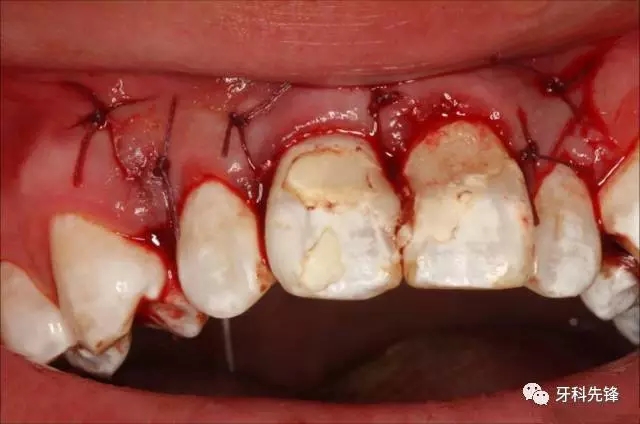

圖13.縫合

圖14.縫合完畢的口內(nèi)照片